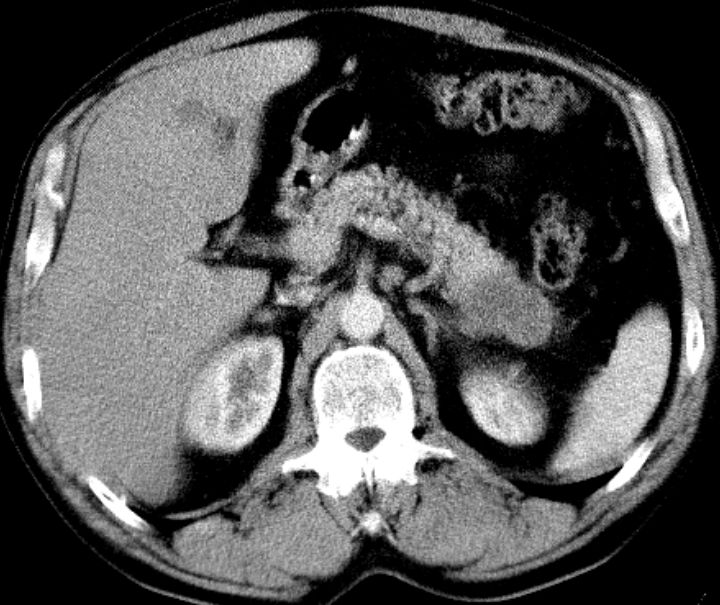

Diagnostik Nach Diagnosesicherung muss die Operabilität geklärt werden. CT ist notwendig, MRT, PET und Sonographie können die Ausdehnung präzisieren.

CT: Pankreasschwanz-Karzinom, Leber- und Lymphknotenmetastasen